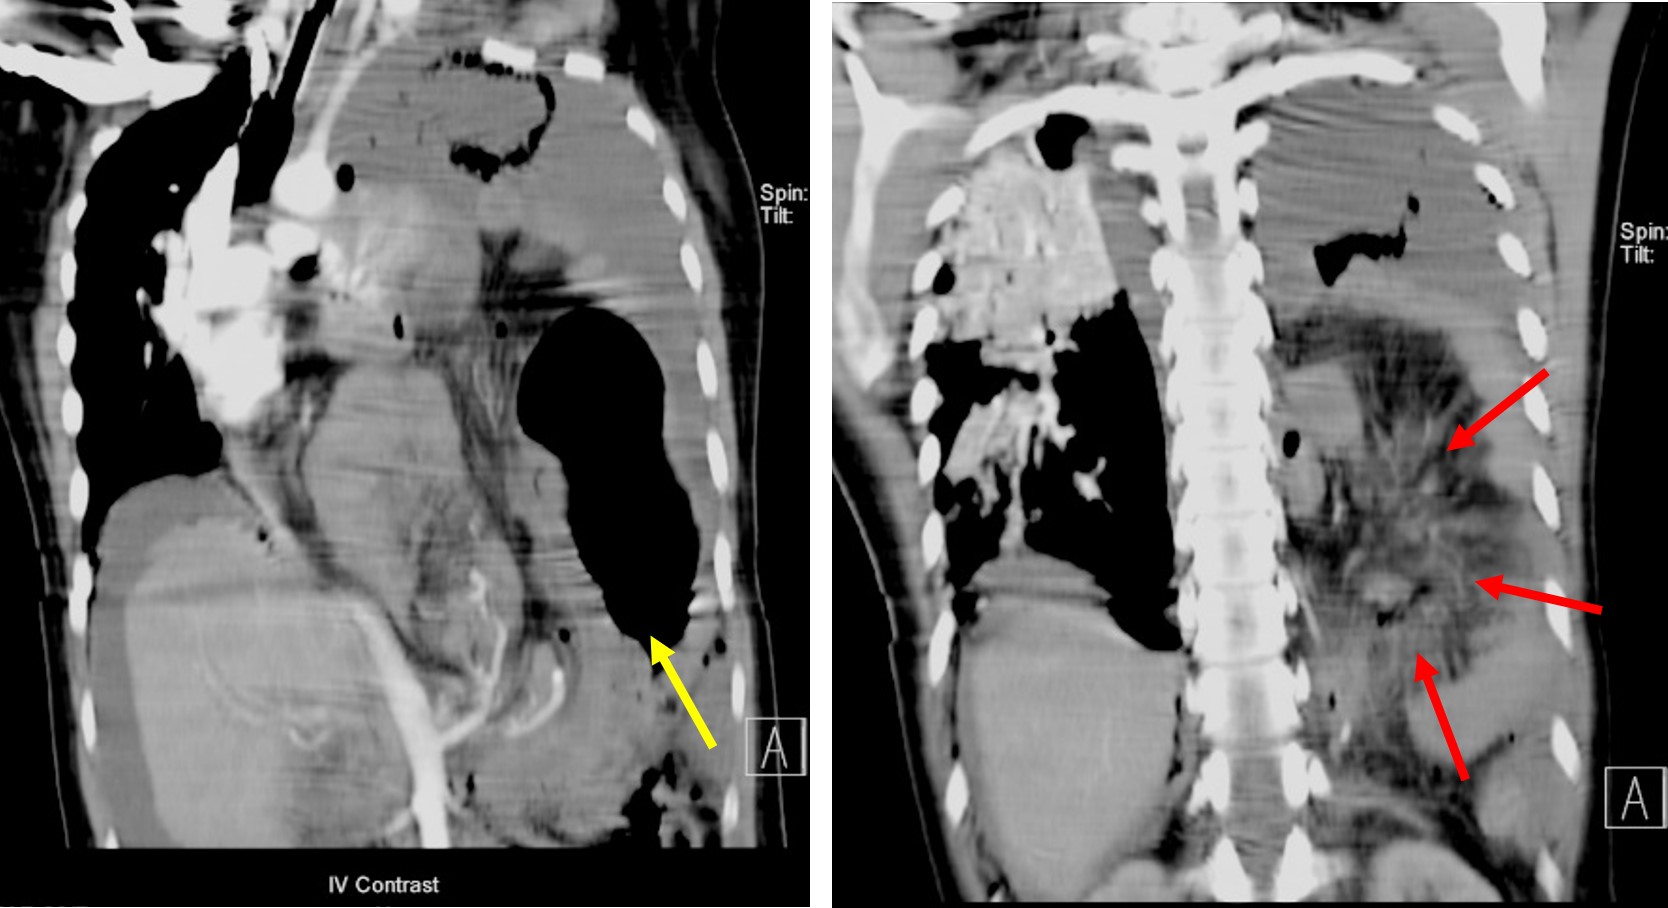

Traumatic diaphragmatic hernia Radiology Cases Diaphragmatic Hernia Usmle A congenital diaphragmatic hernia occurs due to congenital defects in the diaphragm, causing bowel to protrude through the. Here's a short post on the key points about congenital. learn about the causes, types, and radiographic features of congenital diaphragmatic hernia (cdh), a rare fetal. a diaphragmatic hernia is a condition where abdominal contents protrude into the thoracic cavity. Diaphragmatic Hernia Usmle.